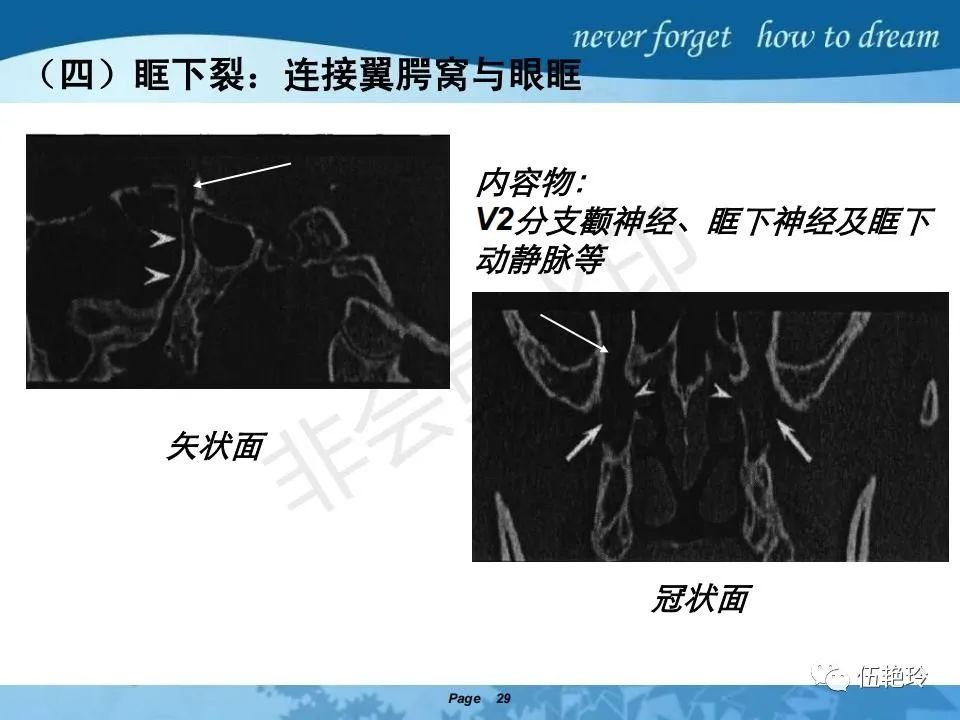

2.2 鼻咽特有的解剖途径:鼻咽癌原发灶循序进展的总途径:鼻腔(47.8%)→翼腭窝(15.2%)→ 眶下裂(3.2%)→眶尖(1.2%)→海绵窦(0.6%)。

2.31 向上颅内:①鼻咽顶壁→破裂孔(岩尖、斜坡)→蝶窦、海绵窦;②鼻咽顶壁→蝶骨基底部→蝶窦、海绵窦;③鼻咽侧壁→茎突前间隙→蝶骨大翼(卵圆孔)→海绵窦;④鼻咽侧壁→茎突前间隙→翼腭窝→ 颞下窝;⑤鼻咽前壁→鼻腔→翼突、翼腭窝→眶下裂→眶尖→海绵窦;⑥鼻咽前壁→鼻腔→上颌窦、筛窦;